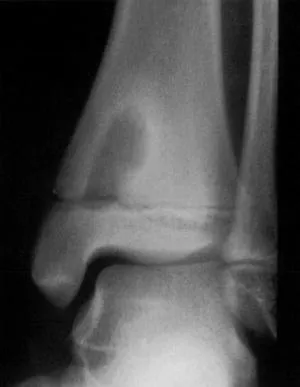

- Chronic osteomyelitis (Brodie's abscess - localized, walled-off).

- Brodie's abscess is a chronic, localized osteomyelitis, appearing as a lytic lesion with sclerotic rim on X-ray.